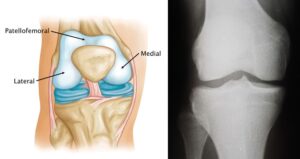

The knee joint is divided into three major compartments:- Medial Compartment: The inner portion of the knee.

- Lateral Compartment: The outer portion of the knee.

- Patellofemoral Compartment: The front portion of the knee, located between the patella (kneecap) and the femur (thighbone).